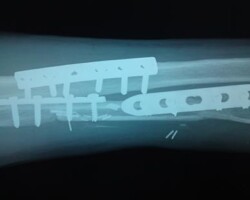

Αγγειούμενη περόνη

Άντρας 21 ετών υπέστη διπολικό κάταγμα της κερκίδας και κάταγμα της ωλένης, που αντιμετωπίστηκε σε περιφεριακό νοσοκομείο. 9 μήνες μετά διαπιστώθηκε ψευδάρθρωση της κερκίδας με οστικό απόλυμα 6,5 εκ. Αντιμετωπίστηκε με τη χρήση αγγειούμενης περόνης, η οποία γεφύρωσε το οστικό έλλειμμα της κερκίδας.